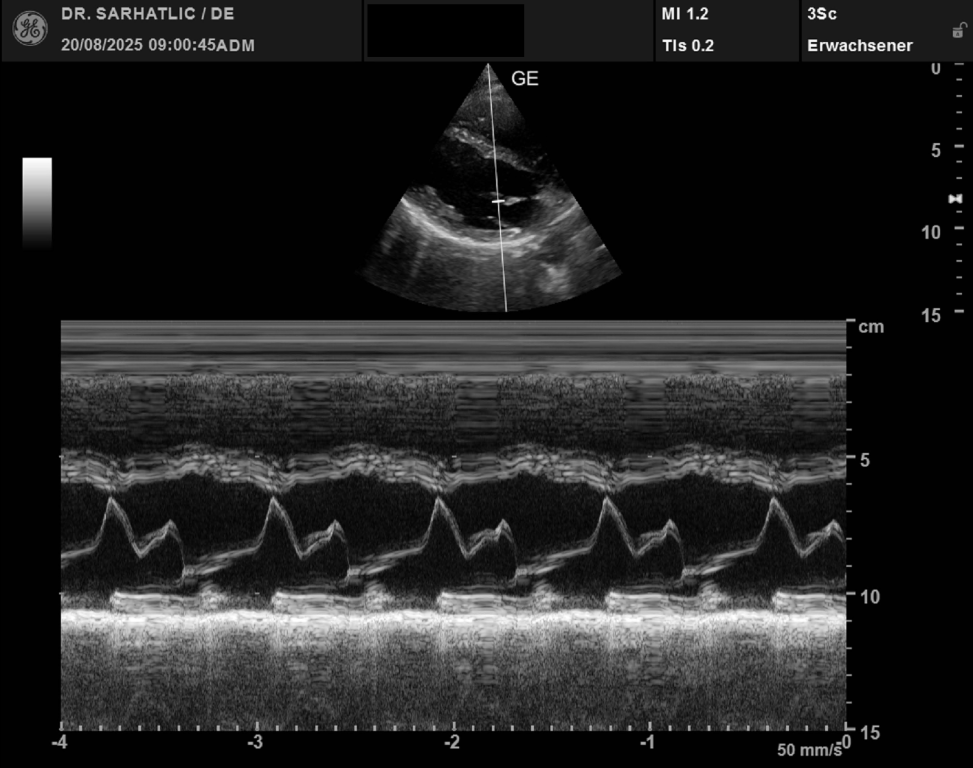

- Ultraschall des Herzens (Echokardiografie)